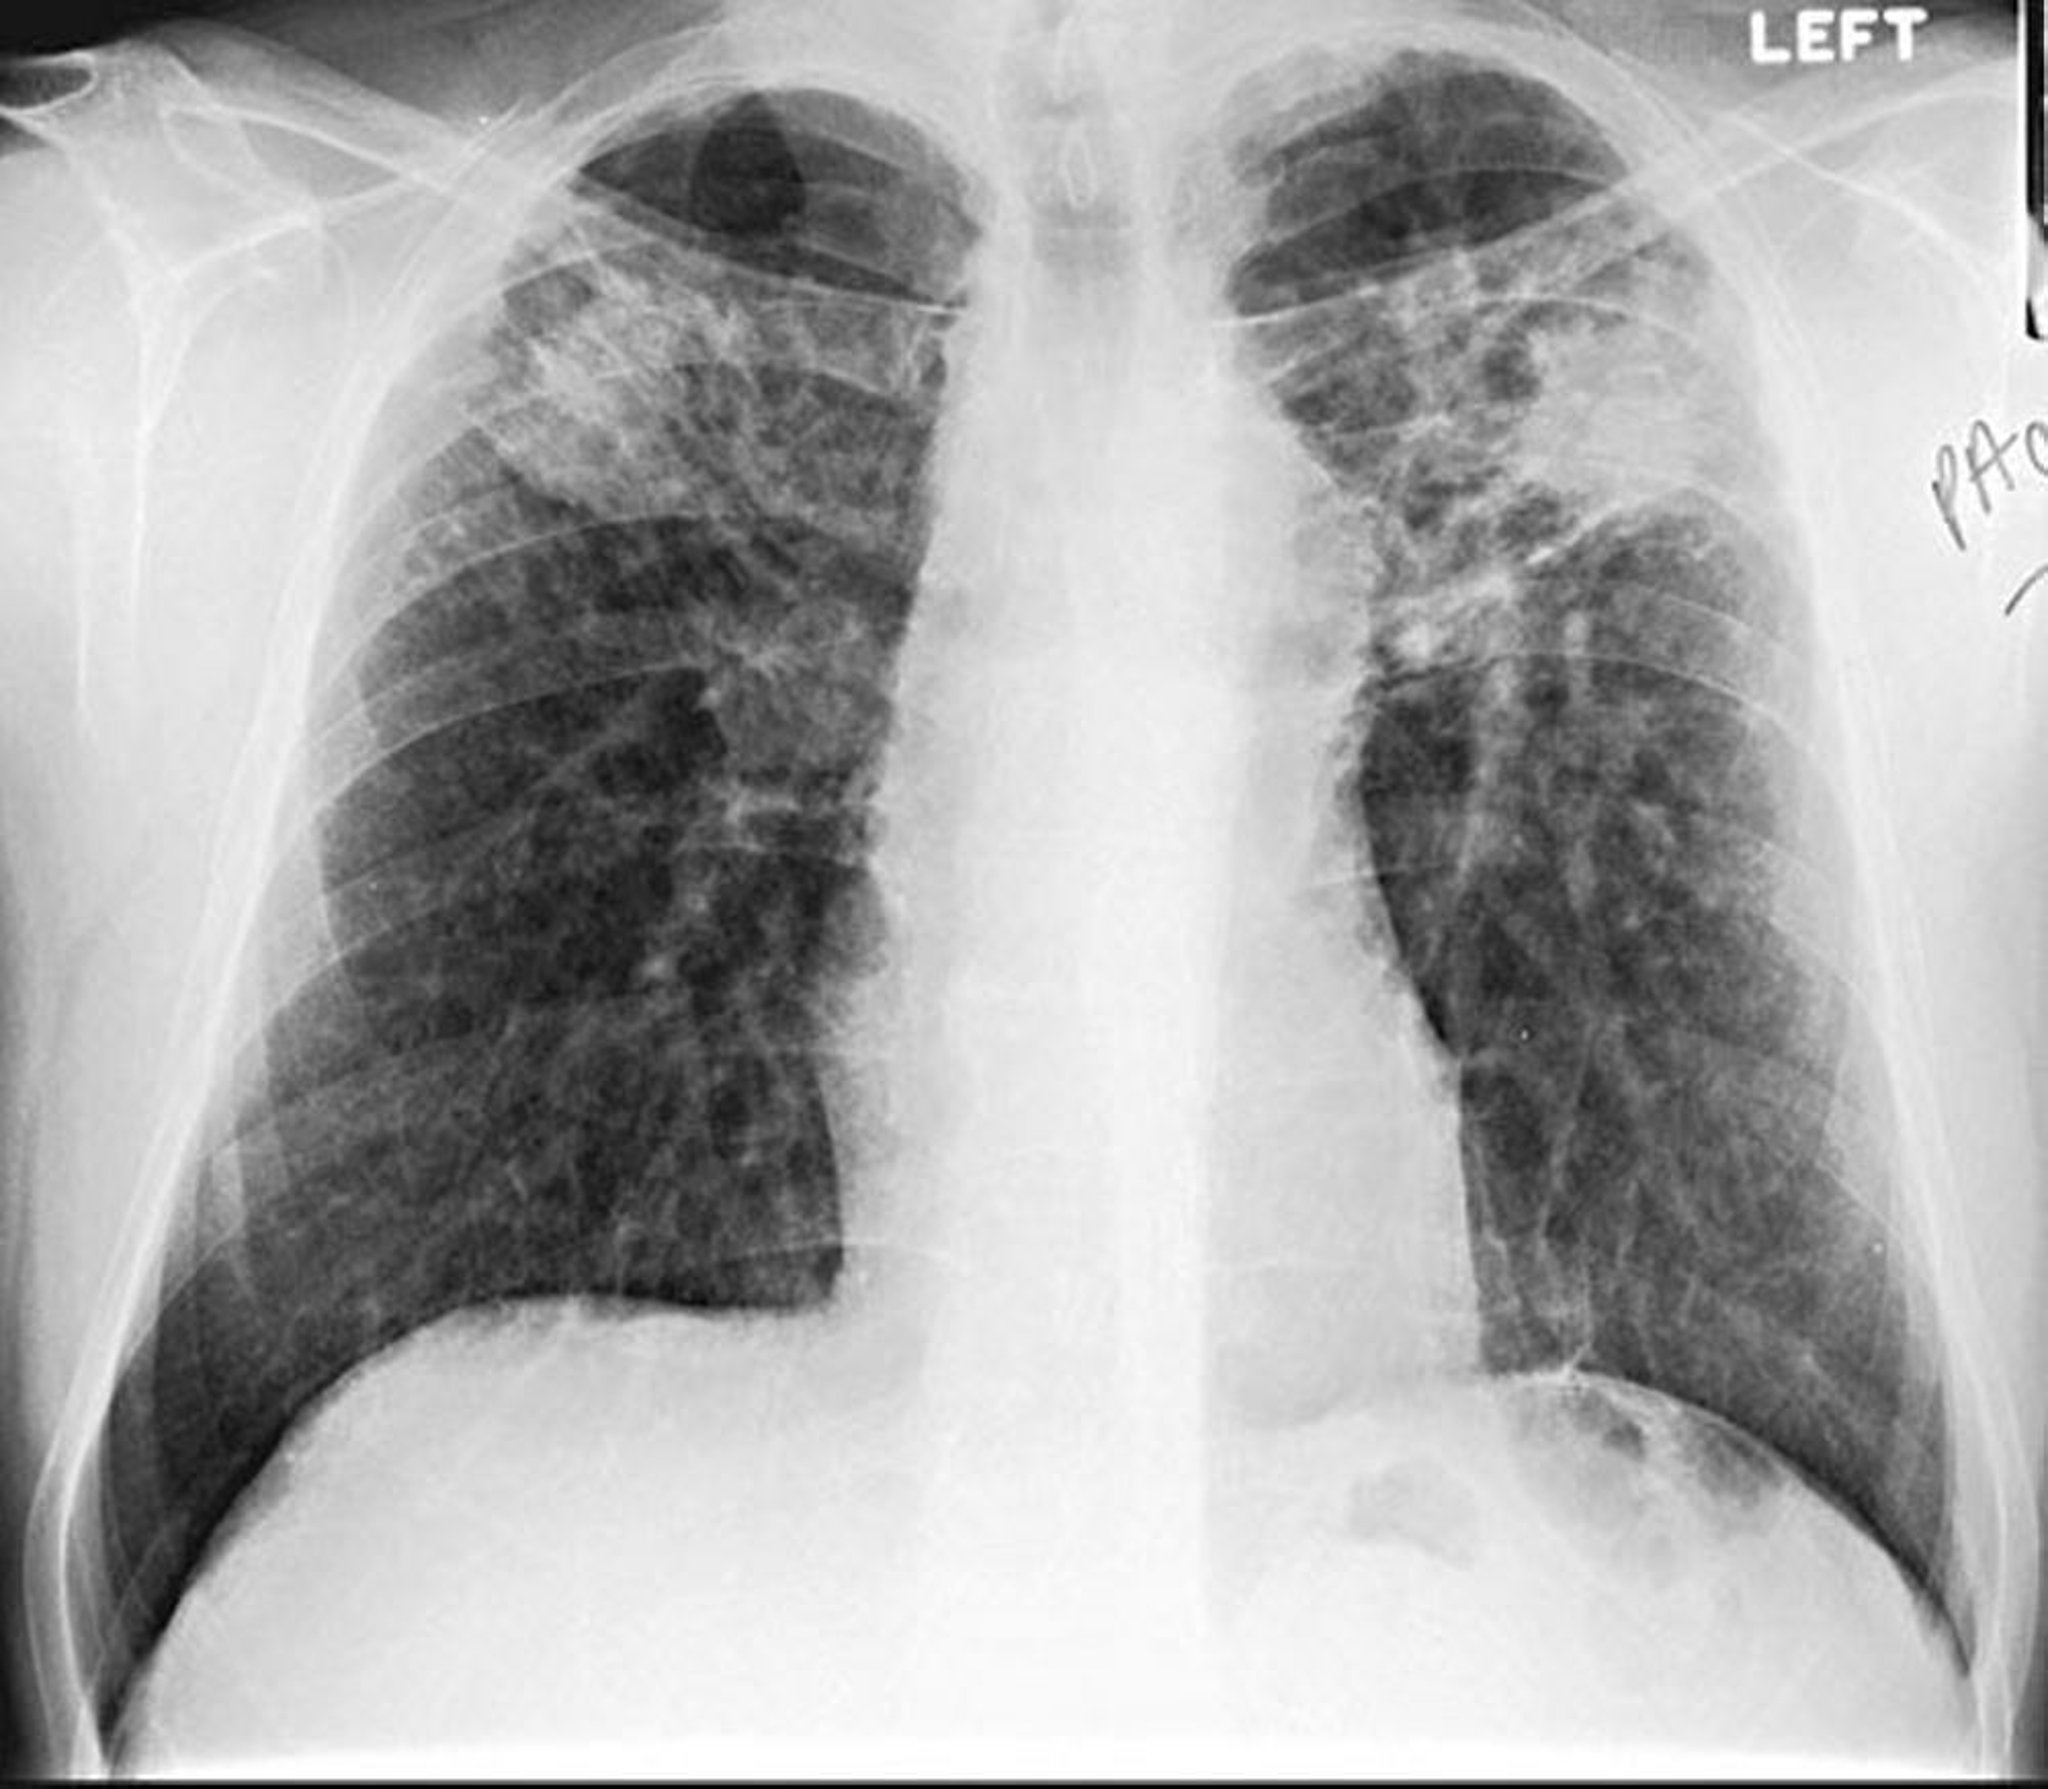

Silicosi, conglomerata

Image courtesy of David W. Cugell, MD.